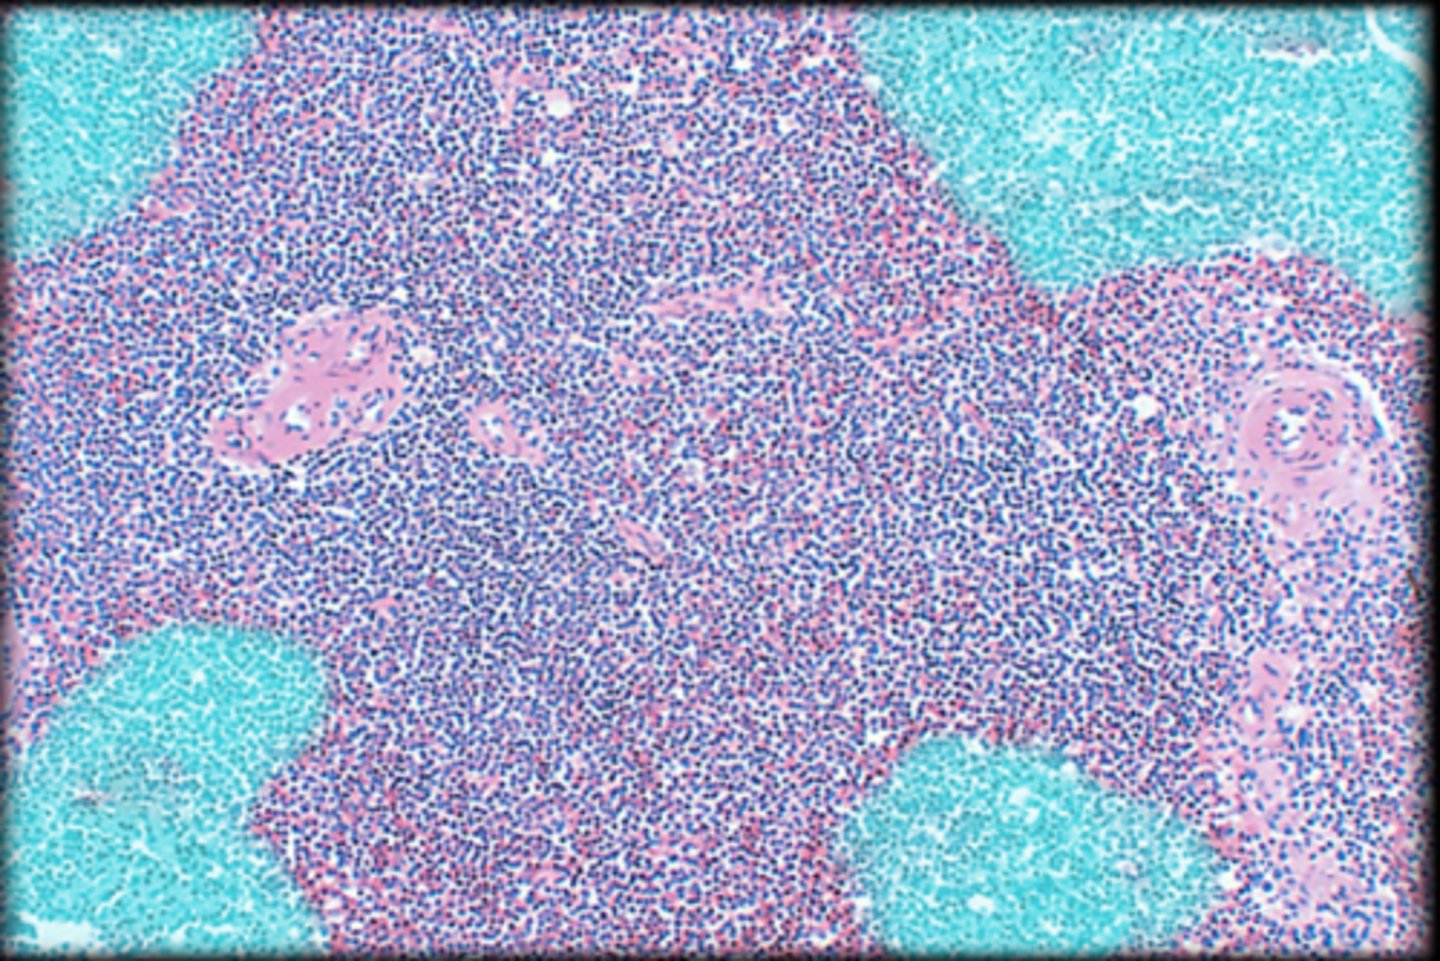

Spleen

central white pulp

red pulp

white pulp